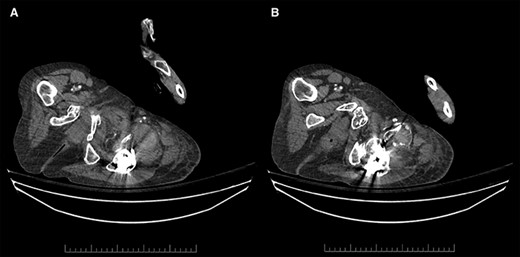

Contrast-enhanced arterial phase axial computed tomographic (CT) images overlying the left hip demonstrating (A) hyperdense material anterior to the left hip in keeping with hematoma (left), and (B) hyperdense material that corresponds to the pseudoaneurysm, which is supplied by a small DFA branch coursing anteriorly and abutting a sharp osseous fragment (right).